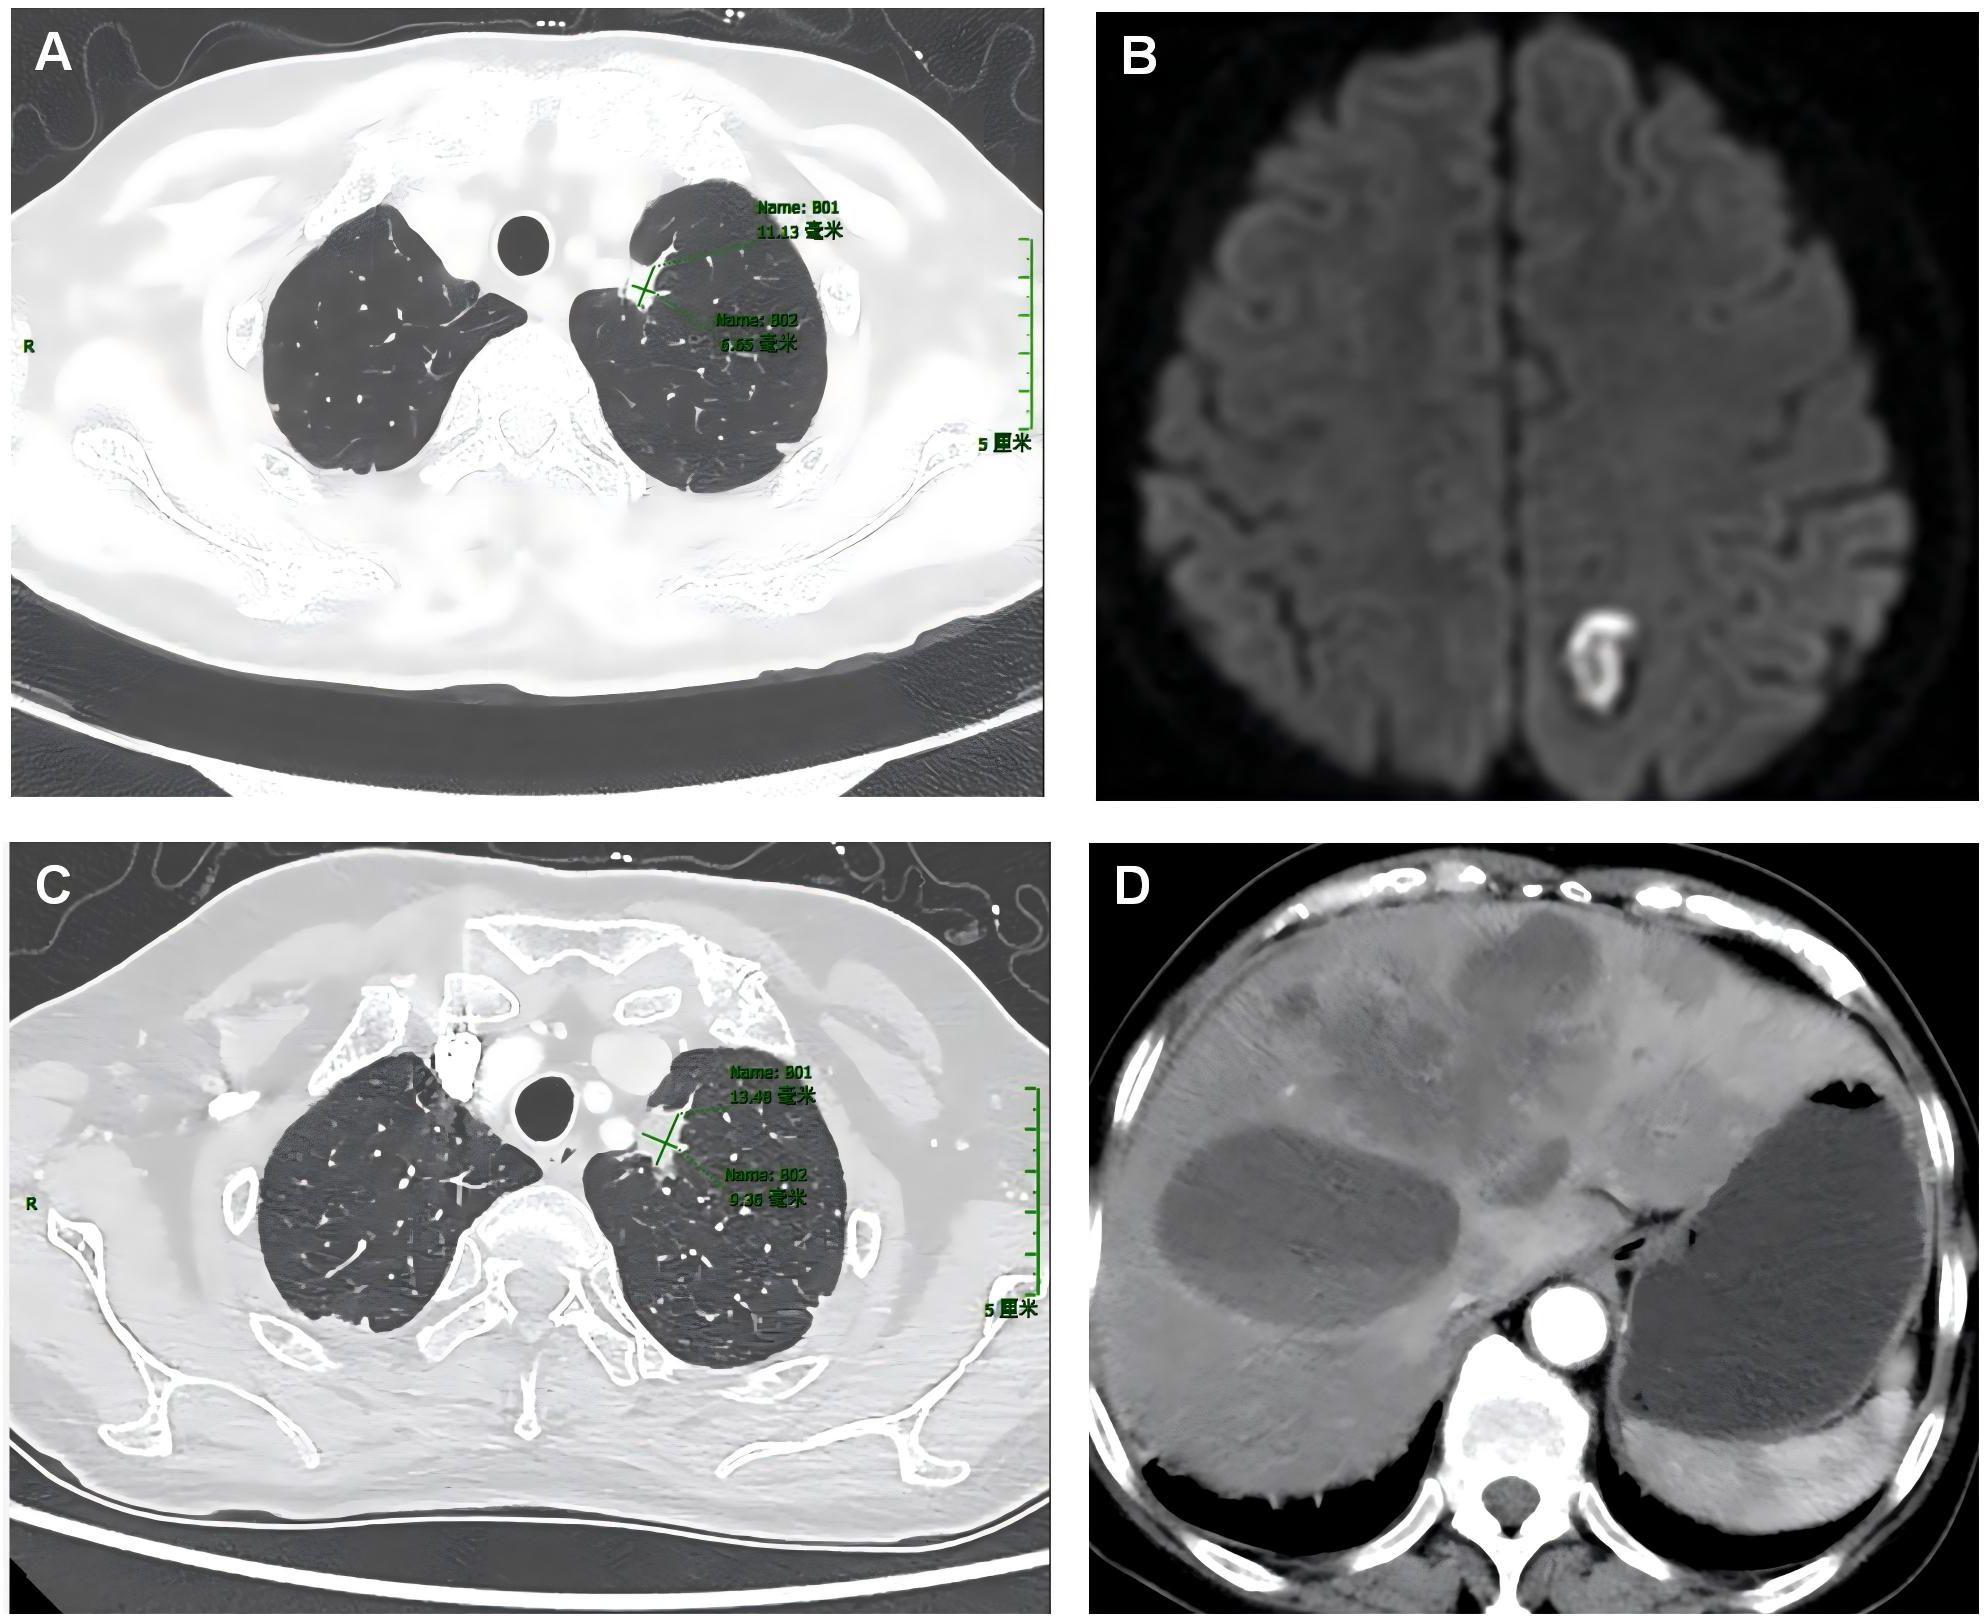

Objective: To investigate the clinical and pathological characteristics of patients with non-small cell lung cancer exhibiting coexistence of NTRK2 fusion and EGFR mutations. Methods: Clinical data as well as histopathological, immunohistochemical, and molecular pathological characteristics of two patients harboring both NTRK2 gene fusions and EGFR gene mutations were retrospectively analyzed, and relevant literature was also reviewed. Results: Both patients were women, aged 57 and 66 years, respectively. The two cases were diagnosed as invasive lung adenocarcinoma, and immunohistochemical staining showed that all tumor cells expressed CK7, Napsin A, TTF-1, and PD-L1. In Case 1, an EGFR mutation in the primary lung lesion, coexistence of NTRK2 fusion and EGFR mutation in liver metastases, and concurrent MET gene amplification and FGFR1 gene mutation were observed. In Case 2, the coexistence of NTRK2 fusion and EGFR mutation was detected in the primary lung lesion. The TMB and microsatellite status were classified as TMB-L and MSS, respectively, in both cases. Case 1 received osimertinib combined with savolitinib, had 33 months of follow-up, and achieved a partial response. Case 2 received furmonertinib and achieved a complete response. Conclusion: NTRK2 fusion coexisting with EGFR mutations is a rare molecular characteristic of non-small cell lung cancer, accompanied by positive PD-L1 expression, and may serve as a promising biomarker for targeted therapy.